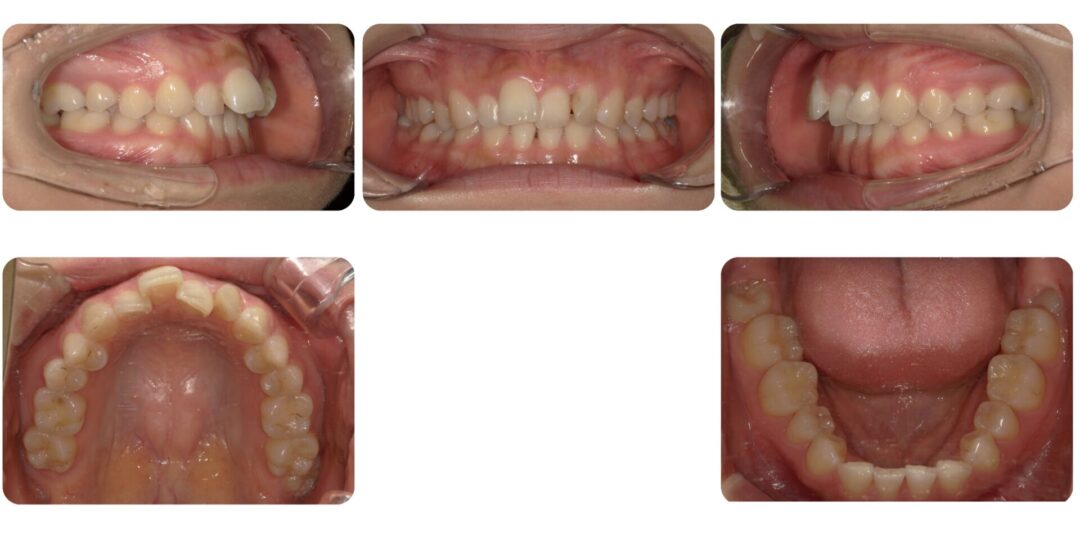

下顎左右犬歯先天性欠如を伴う叢生|初診時24歳

矯正治療後

治療内容

成人歯科矯正 上顎左右第一小臼歯抜歯 マルチブラケット装置

治療期間

3年4ヶ月